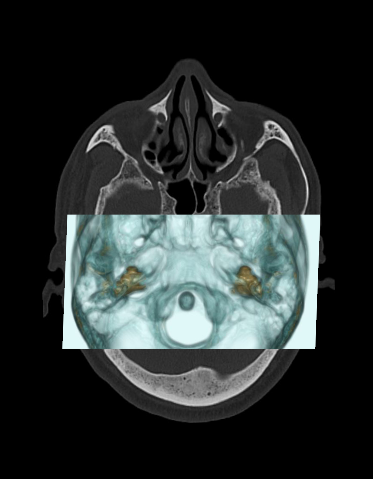

- Plan the scan range to include the temporal bone that covers superiorly from the bony part of the IAM-covering the most superior mastoid air cell to mastoid tip inferiorly.

- Maximum slice thickness of 1mm in axial and coronal planes, reconstructed in bone window (WW:4500, WL:450) to show both canals in the same plane.

- Axial images of the posterior fossa in soft-tissue window (WW:400, WL:40) with 1mm slice thickness.